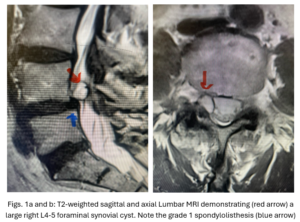

This 54-year-old female with a long history of low back pain presents with three weeks of a progressive right footdrop with associated numbness and tingling of the right leg. In addition, she had right lateral hip pain down to the dorsum of her foot. She first noticed her right foot slapping the floor when she walked. She had no prior trauma or unusual activity before this began. Her chiropractor, who had treated her back pain for a long time, first noticed the foot drop and referred her for further evaluation. She presented with ⅖ strength in her right dorsiflexor. MRI revealed a large right L4-5 foraminal synovial cyst with some mass-effect on the thecal sac. (Fig. 1) She also had an associated grade 1 spondylolisthesis. Because the cyst was more foraminally-oriented, it had the majority of its effect on the right L4 nerve root. It was felt the patient required surgery to attempt to reverse her weakness. We performed a decompressive laminectomy at L4, removing the inferior facet process on the right in order to gain lateral and foraminal access to the right L4 nerve root. In the lateral recess there was a heap of inflammatory tissue which we entered, revealing the cyst. The medial wall was stuck to the dura. We internally decompressed the cyst which was mainly gelatinous material with some fluid. We dissected and removed as much of the cyst we could safely remove but left the medial wall for fear of removing it would cause a CSF leak, upon removing the bulk of the cyst we encountered anteriorly the descending and exiting right L4 nerve root which was purplish in color and clearly inflamed. We performed a generous foraminotomy of the right L4 as well as the right L5 nerve root. We also performed an instrumented fusion at L4-5 (Fig. 2).